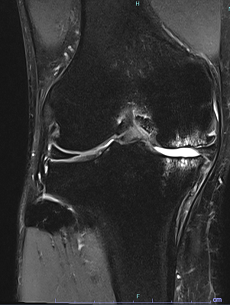

変形性膝関節症、関節リウマチ、外傷による後遺症などで、リハビリテーションや注射などの保存的な治療の効果が得られない状態までダメージを受けてしまった膝関節は、症状が回復する可能性が低く、日常生活が制限されるほどの非常に強い痛みを伴います。特に軟骨が完全に欠損してしまった場合は細胞治療などを行っても軟骨は完全には再生しないため効果は乏しいです。